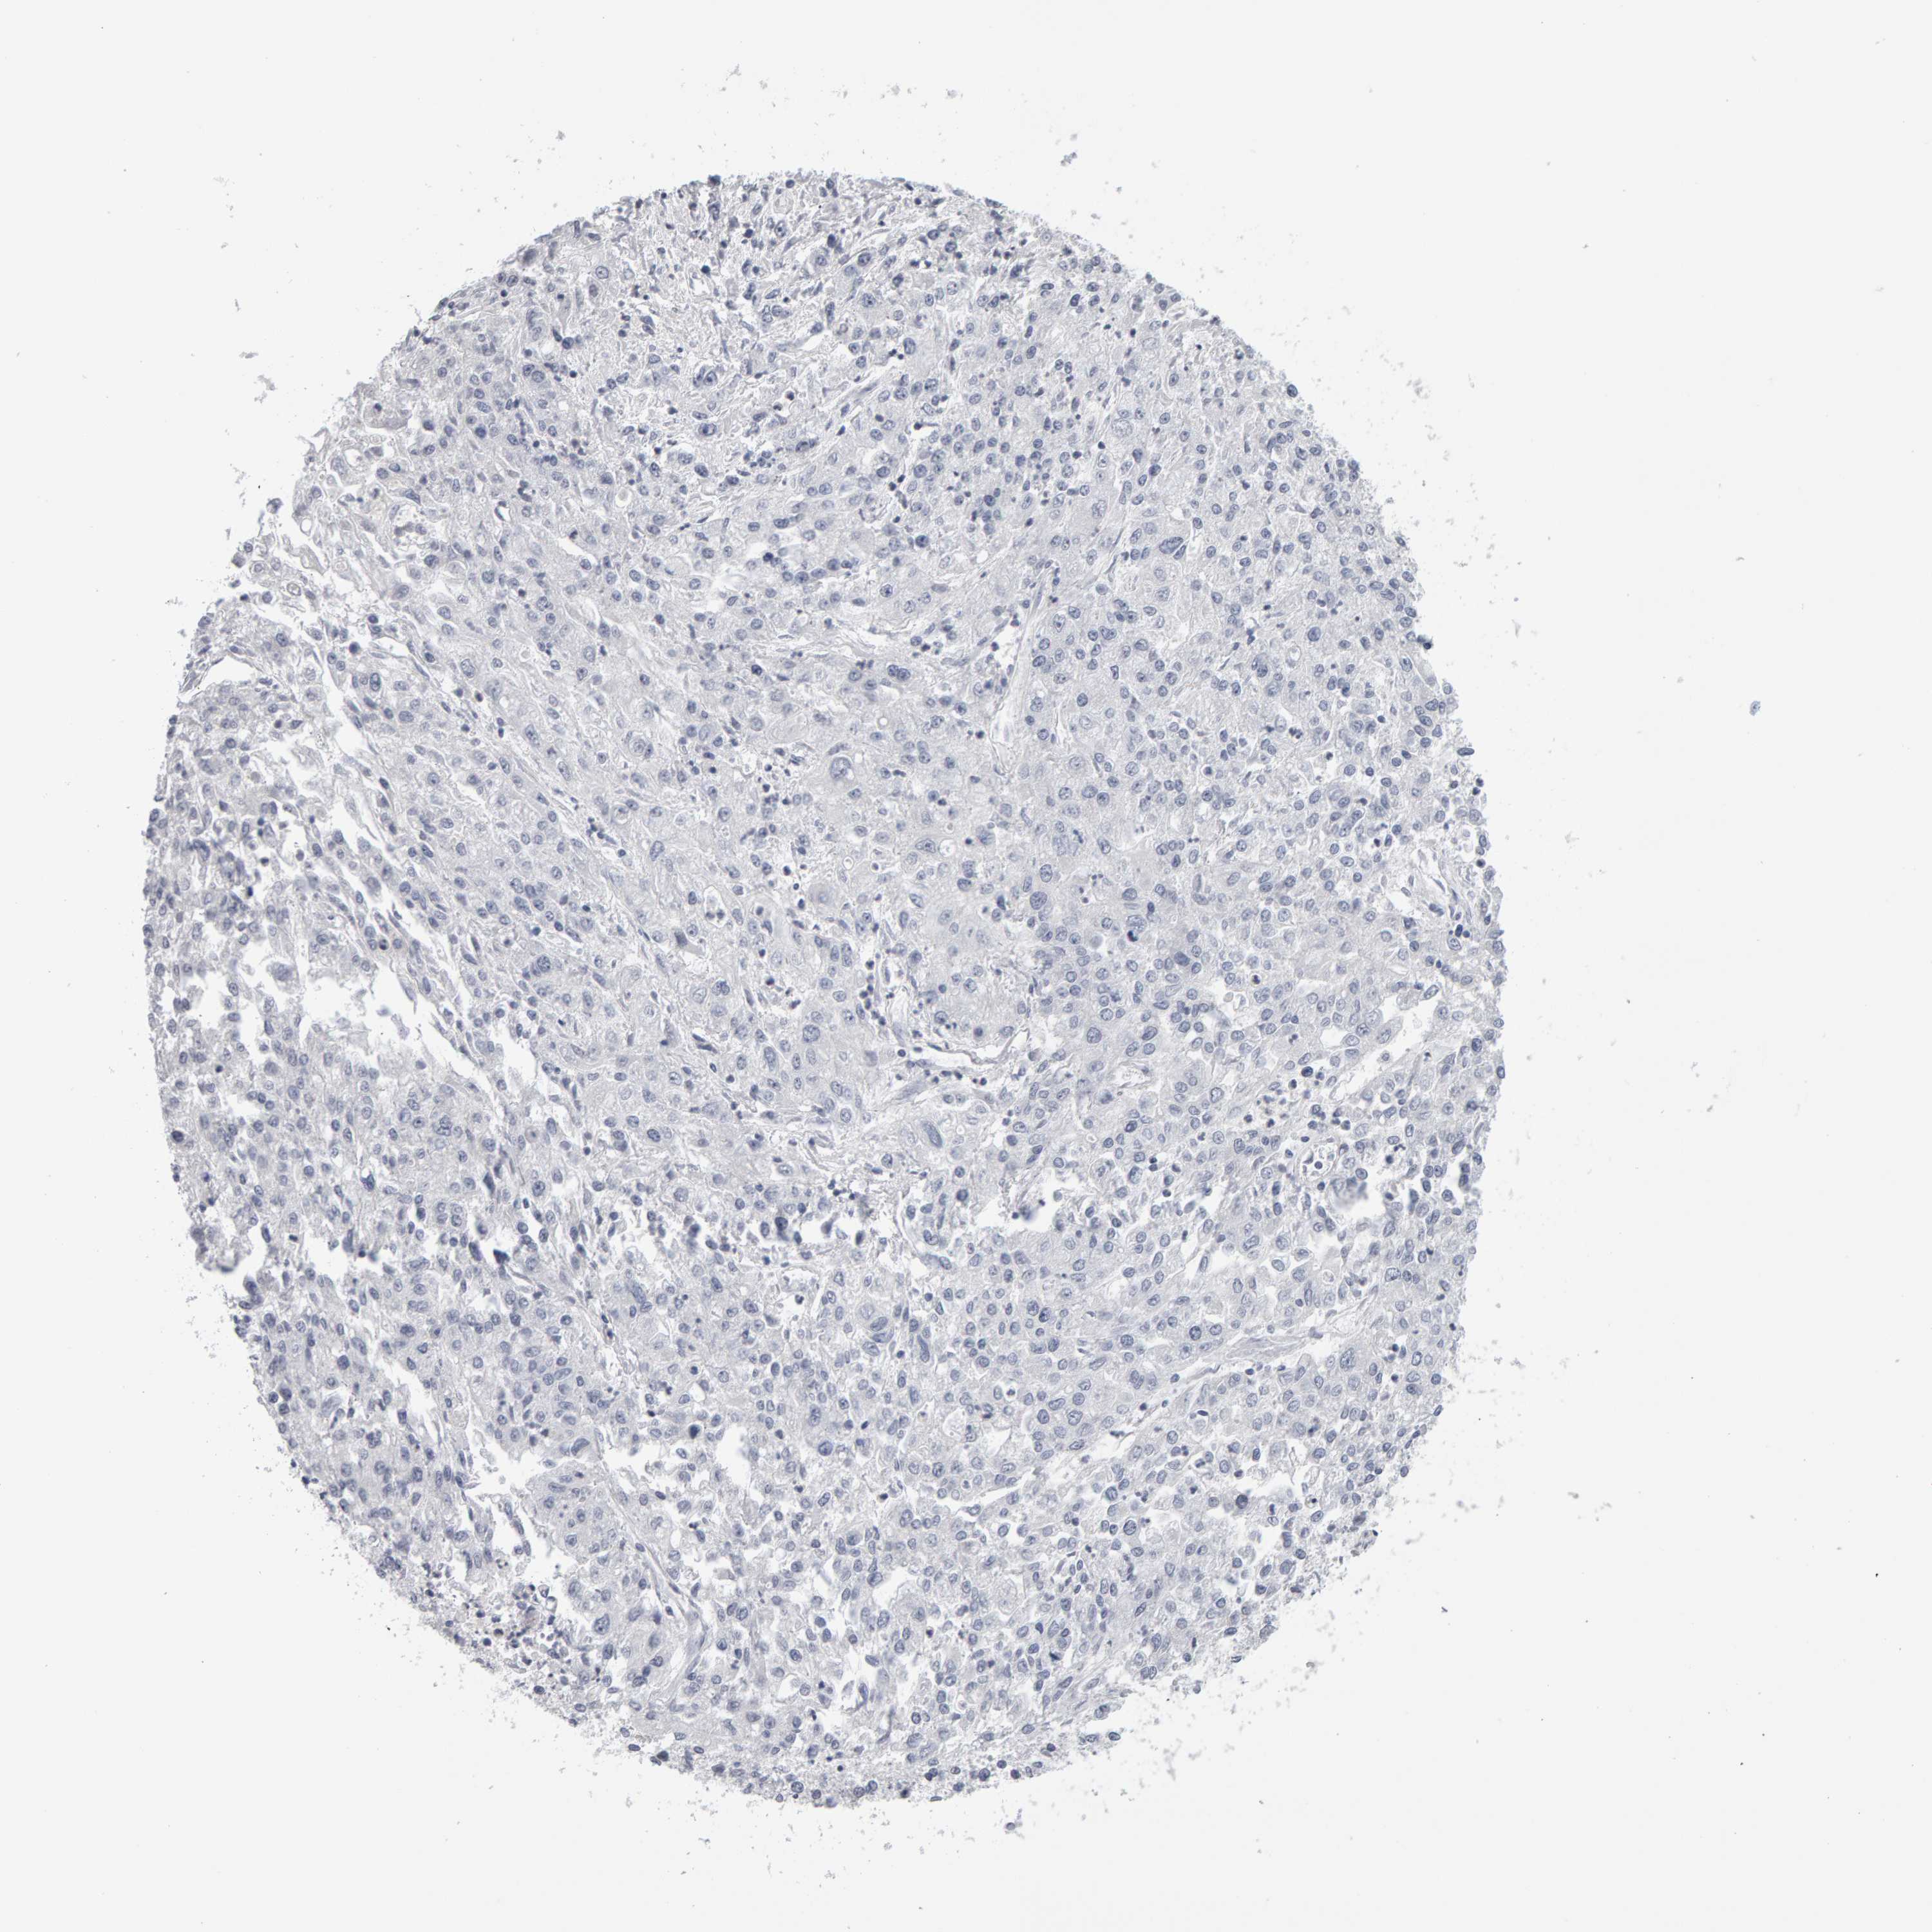

ENDOMETRIAL CANCER - Protein expressioni

A mouse-over function shows sample information and annotation data. Click on an image to view it in a full screen mode. Samples can be filtered based on level of antibody staining by selecting one or several of the following categories: high, medium, low and not detected. The assay and annotation is described here.

Note that samples used for immunohistochemistry by the Human Protein Atlas do not correspond to samples in the TCGA dataset.

Antibody stainingi

Antibody staining in the annotated cell types in the current human tissue is reported as not detected, low, medium, or high, based on conventional immunohistochemistry profiling in selected tissues. This score is based on the combination of the staining intensity and fraction of stained cells.

Each image is clickable and will lead to virtual microscopy that enables deeper exploration of all samples and also displays staining intensity scores, fraction scores and subcellular localization as well as patient and tissue information for each sample.

Antibody HPA023804

Antibody HPA075766

Staining

High

Medium

Low

Not detected

Intensity

Strong

Moderate

Weak

Negative

Quantity

>75%

75%-25%

<25%

None

Location

Nuclear

Cytoplasmic/membranous

Cytoplasmic/membranous,nuclear

Adenocarcinoma, NOS

Adenoma, NOS